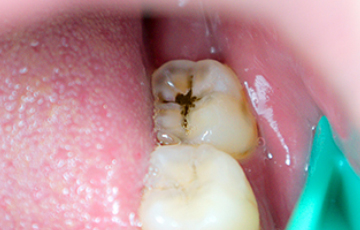

충치치료란?

염증을 제거한 후 인체에 무해한 치과 재료를 빈 공간에 채워 넣어 남아있는 치아를 보호해주는 치료입니다.

한번 생긴 충치는 자연회복이 되지 않으므로 조기에 발견하여 치료하는 것이 좋습니다.

충치 때문에 생기는 통증은 지속적이지 않고 생겼다가도 사라지는 걸 반복하기 때문에 치과 진료를 미루는 경우가 많습니다.

하지만 충치는 전염성이 강해 주변 치아까지 썩게 만들거나 신경까지 침범할 수 있어 발견 즉시 치료를 받는 것이 좋습니다.

충치가 심해질수록 치아의 삭제량도 많아지고 치료 비용 또한 올라가게 되니 조기에 적절한 치료를 받는 것이 중요합니다.

• 법랑질 충치

치아 겉면인 법랑질의 충치로

통증이 거의 없습니다.

레진진료

• 상아질 충치

법랑질 안쪽에 있는 상아질까지

충치가 진행되어 뜨겁거나

차가운 음식을 먹으면

시린 증상이 나타납니다.

인레이

• 치수염 충치

상아질 안쪽 신경까지

염증이 진행되어

극심한 통증으로

참기 어려운 정도가 됩니다.

신경치료 + 크라운